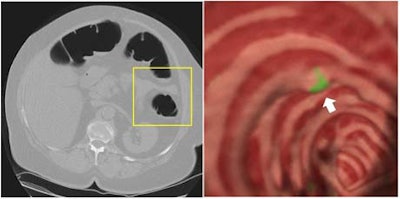

![]() |

The shape-based analysis is applied to the entire colon, which shows the "polyp candidates" in green. However, at this stage there are several false positives.

"In order to remove these false positives, we apply a texture analysis inside the lesion," he told the RSNA audience. "Warped curves are generated by decision analysis as a decision boundary between the two. By eliminating one portion of the curve, we can eliminate a large number of false positives."